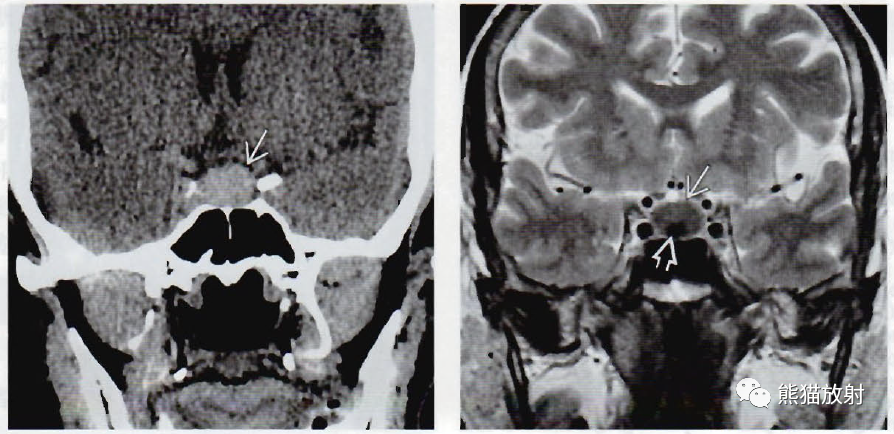

(左) 一头痛患者,冠状位NECT显示高信号的鞍内肿块,稍向鞍上延伸。

(右) 同一位患者,冠状位T2WI显示囊肿主要呈低信号,注意囊内结节(空箭)。术中发现为Rathke裂囊肿。